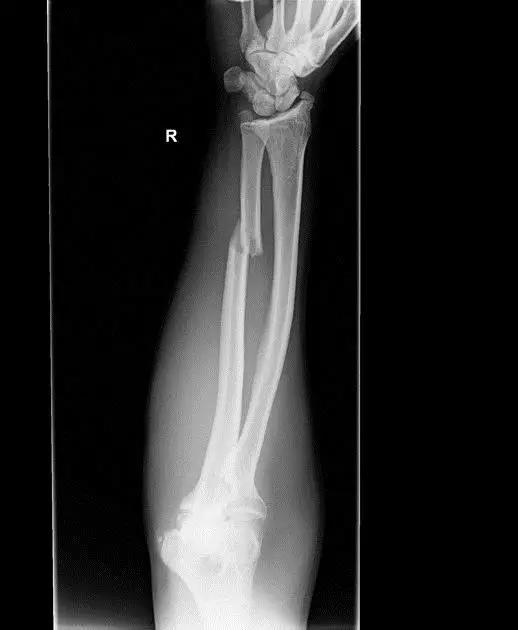

9. Monteggia 骨折(孟氏骨折)

尺骨近端 1/3 骨折合并桡骨头半脱位。

(来源:Radiopaedia)

成人 Monteggia 骨折

儿童 Monteggia 骨折